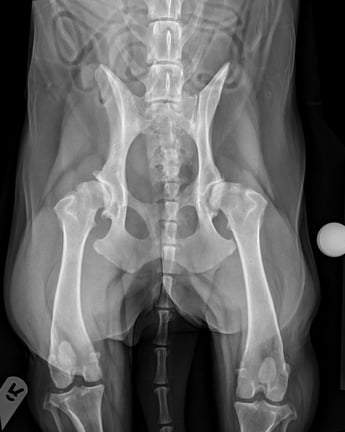

Radiographs of the stifles and pelvis showed bilateral hip dysplasia with signs of OA. An orthopaedic referral assessment with a specialist team was organised, and robenacoxib, gabapentin and paracetamol were prescribed until further investigation.

The patient underwent radiography under sedation (0.01mg/kg medetomidine, 0.2mg/kg butorphanol). The radiographs showed left pelvic OA, right OA and HD with a shallow and remodelled acetabulum and femoral head (Figure 2).